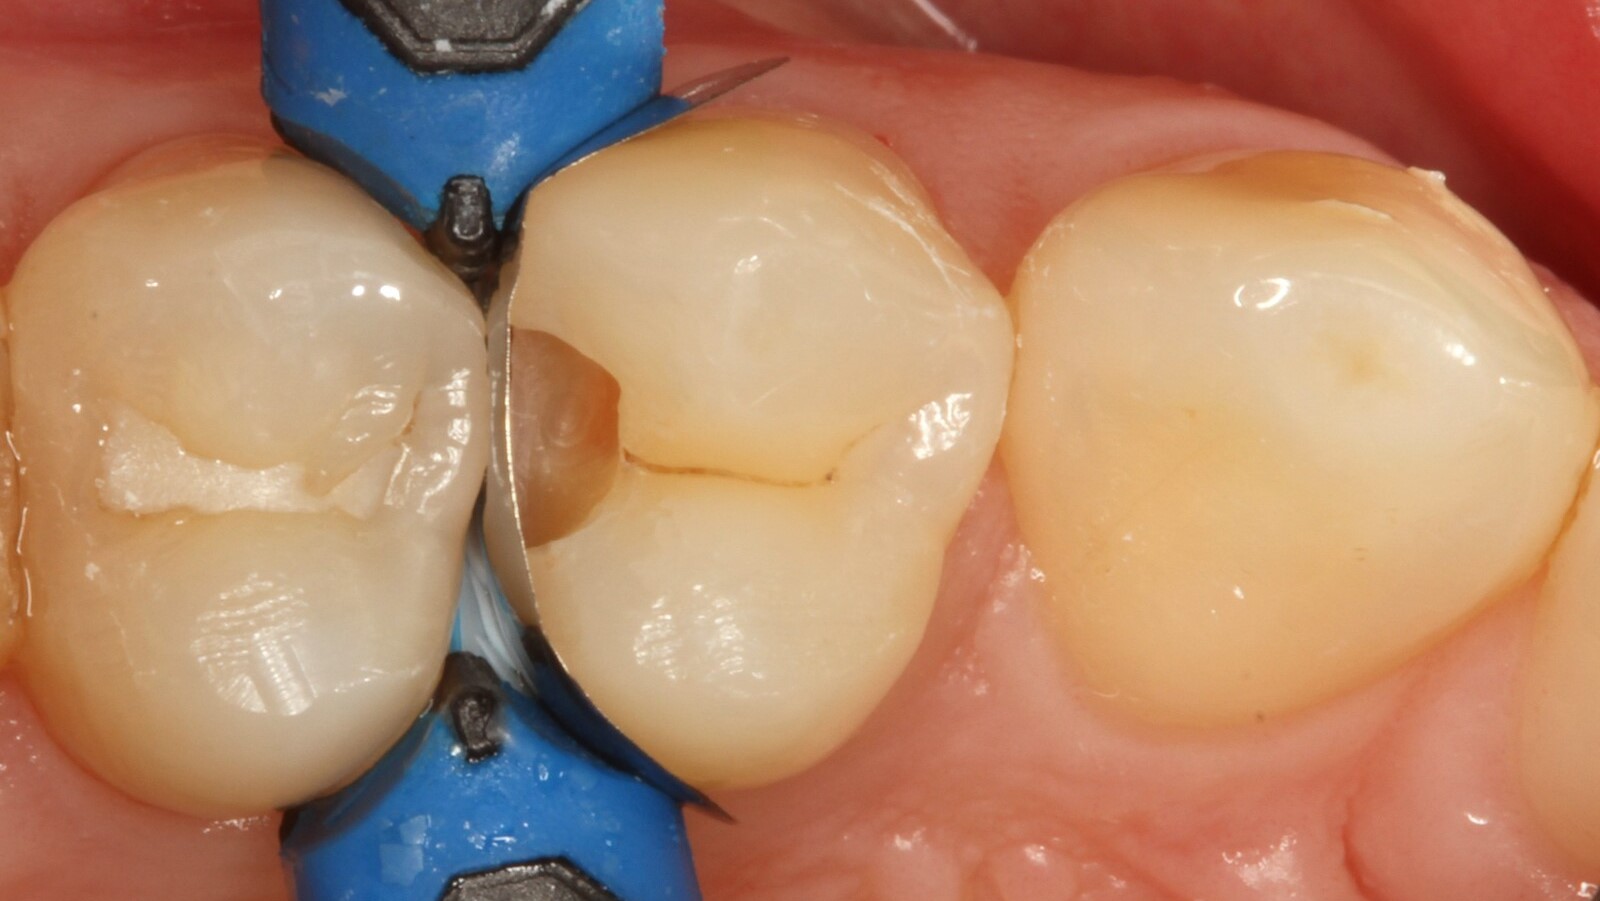

Le professeur Ernst a d'abord identifié les caries non visibles et a ouvert la lésion carieuse pour montrer le problème au patient (Fig. 1-2). Il a ensuite excavé la carie, préparé la cavité et placé une matrice sectionnelle (Fig. 3) avant de sceller la cavité avec de l'adhésif (Fig. 4). En une seule étape, il a rempli la cavité avec Venus Bulk Flow ONE (Fig. 5). Une fois la restauration terminée, le Pr Ernst l'a polie (Fig. 6) et a pris une radiographie de contrôle, qui montre également l'excellente radiopacité de Venus Bulk Flow ONE (Fig. 7).